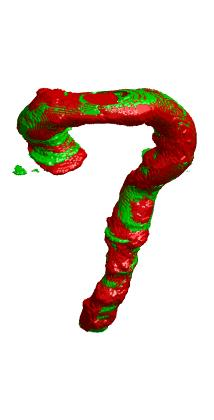

Deep Convolutional Neural Networks (DCNNs) are used extensively in biomedical image segmentation. However, current DCNNs usually use down sampling layers for increasing the receptive field and gaining abstract semantic information. These down sampling layers decrease the spatial dimension of feature maps, which can be detrimental to semantic image segmentation. Atrous convolution is an alternative for the down sampling layer. It increases the receptive field whilst maintains the spatial dimension of feature maps. In this paper, a method for effective atrous rate setting is proposed to achieve the largest and fully-covered receptive field with a minimum number of atrous convolutional layers. Furthermore, different atrous blocks, shortcut connections and normalization methods are explored to select the optimal network structure setting. These lead to a new and full-scale DCNN - Atrous Convolutional Neural Network (ACNN), which incorporates cascaded atrous II-blocks, residual learning and Fine Group Normalization (FGN). Application results of the proposed ACNN to Magnetic Resonance Imaging (MRI) and Computed Tomography (CT) image segmentation demonstrate that the proposed ACNN can achieve comparable segmentation Dice Similarity Coefficients (DSCs) to U-Net, optimized U-Net and hybrid network, but with significantly reduced trainable parameters due to the use of full-scale feature maps and therefore computationally is much more efficient for both the training and inference.